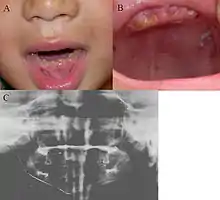

Oral photographs from an individual with Dentinogenesis imperfecta

This condition can cause teeth to be discolored (most often a blue-gray or yellow-brown color) and translucent, giving teeth an opalescent sheen.[2][3][8][5][9] Teeth are also weaker than normal, making them prone to rapid wear, breakage, and loss.[2][3][4][5][8] These problems can affect baby (primary/deciduous) teeth alone, or both baby teeth and adult (permanent) teeth, with the baby teeth usually more severely affected.[5][8]

Clinical features include:

• Discoloured teeth - teeth may be amber, brown, blue or opalescent

• Bulbous shape to the tooth crown due to cervical constriction

• Tooth wear/Non-carious tooth surface loss (NCTSL) - due to the poorly mineralised dentine, the enamel of the tooth is unsupported and subsequently shears or chips off as it is subjected to biting forces. This exposes the underlying poorly mineralised dentine which is less resistant to wear. Therefore, features of abrasion and attrition may become apparent.

• Reduction in occlusal vertical dimension (OVD) - this is secondary to the tooth wear/NCTSL. A reduced OVD can lead to craniofacial dysgnathia, poor tooth aesthetics, and disorders during chewing, swallowing, speaking and eating.[2][3][4][5][8]

The baby (primary) teeth are usually more severely affected than adult (permanent) teeth.[3][5][8]

Radiographic presentation

Radiographic features include:

• Bulbous shape of tooth crown with pronounced cervical constriction

• Small pulp, or total pulp obliteration

• Small or obliterated root canal

• Presence of pulp stones

• Narrow and small roots

• Periapical radiolucency without any evidence of clinical pathology such as tooth decay (dental caries)[2][3][5][14]